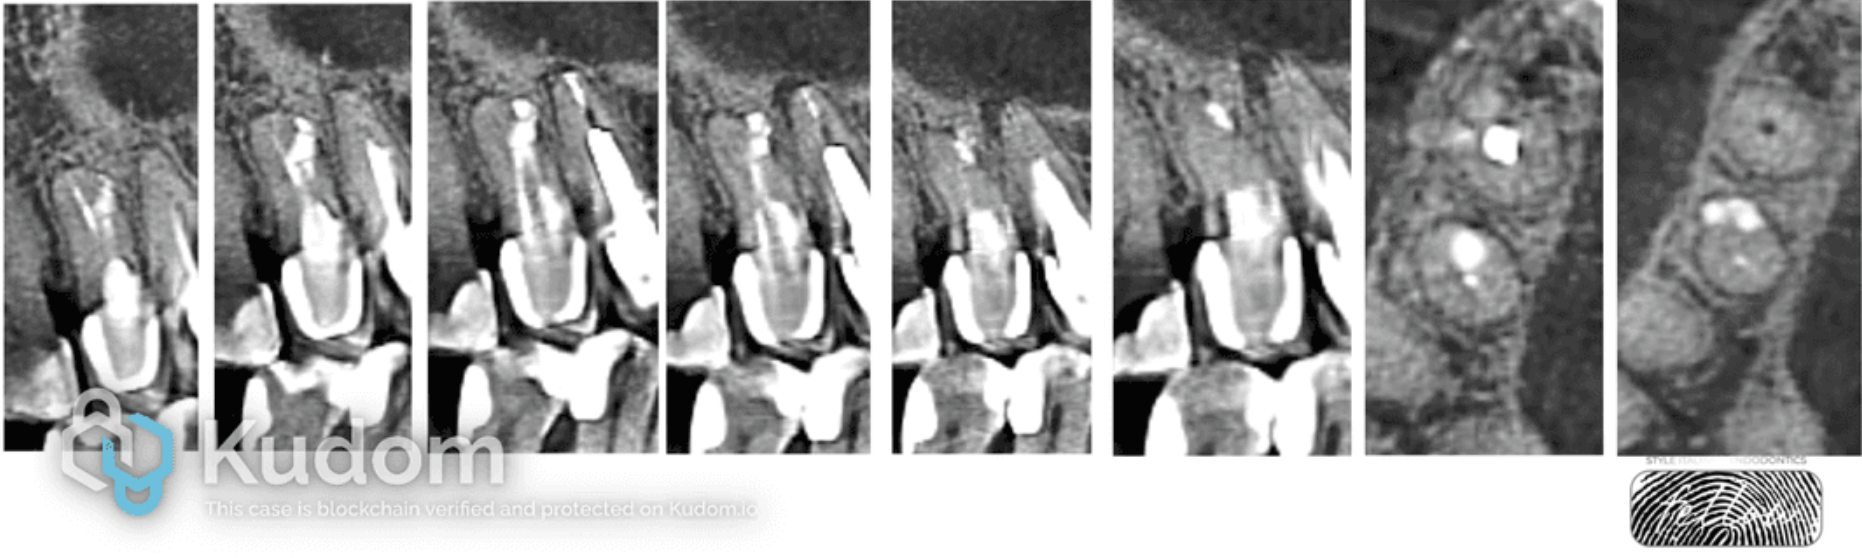

Fig. 9

Dynamic radiographic diagnostics over 4 years also shows excellent results. Healing of the periapical tissues is observed.

Fig. 10

After 5 years, a CBCT scan was performed, revealing complete elimination of the pathological focus with restoration of the lamina dura and a normal periodontal ligament space around the entire root perimeter. This indicates the successful outcome of the ROOT-CROWN-TISSUE concept.